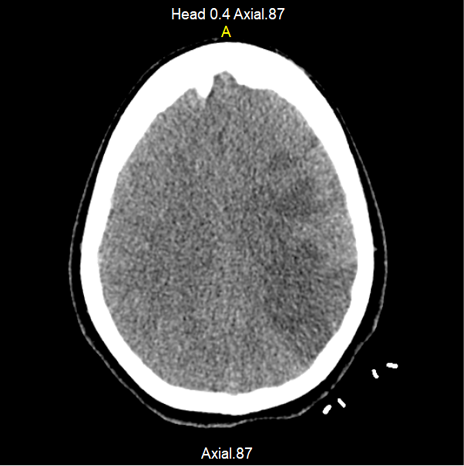

Radiología intervencionista decide realizar embolización, posicionándose stent en cuello de aneurisma, con colocación de 5 coils de 2x10 mm en su interior. Al realizar control angiográfico, se observó la presencia de múltiples elementos radiolúcidos en relación con trombos en posición proximal del stent, por lo que se administró bolo IV de alteplasa de 20 mg y se continuó con 50 mg en infusión continua por 24 horas, trasladándose a Unidad de Cuidados Intensivos (UCI), donde ingresa con choque de posible origen neurogénico (dado el evento presentado) y se inicia manejo de su choque y neuroprotección bajo ventilación mecánica invasiva y sedación profunda (con RASS meta de -5 puntos) con fentanil, midazolam, y soporte vasopresor con norepinefrina. En la TAC de cráneo simple, se observó hipodensidad cortico-subcortical con compromiso fronto-parieto-temporal izquierdo, de etiología vascular isquémica, asociada a edema perilesional con cierre ventricular completo (Figura 1), adicionándose al manejo manitol al 20 % y fenitoína. Desde el ingreso a UCI recibió tromboprofilaxis con medias antiembólicas. Evolución tórpida, persiste con inestabilidad hemodinamica, y adicionalmente presenta disminucion súbita y severa en índices de oxigenación (PaO2/FiO2 = PaFi de 101.2, con valores previos de PaFi mayores de 250) sin alteración en reactantes de fase aguda, ni fiebre, por lo anterior se sospecha embolia pulmonar de alto riesgo y se solicita TAC de torax con protocolo para TEP la cual reportó múltiples defectos de llenado bilaterales a nivel de las arterias pulmonares y sus ramas segmentarias, con evidencia de trombo a nivel de bifurcación del tronco de la arteria pulmonar (Figura 2), hallazgo que coincide con tromboembolismo pulmonar de alto riesgo, dada la repercusión hemodinámica. (PESI score de 155 puntos).

Figura 2. Trombo en bifurcación de arteria pulmonar (flecha). Fuente: Departamento de radiología, Hospital Universitario de Santander.